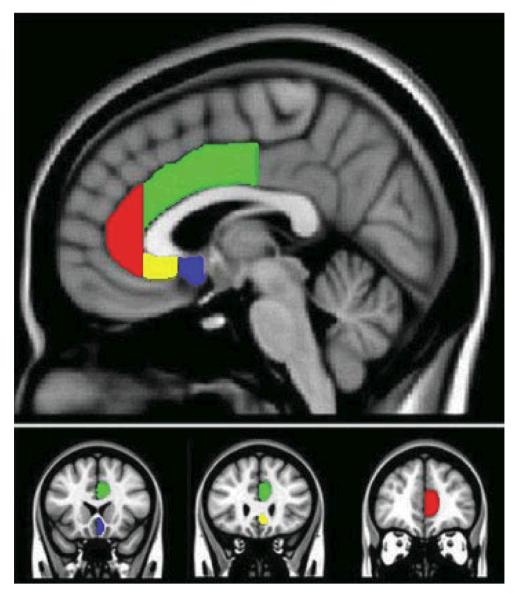

For posterior subgenual ACC: anterior boundary began where the putamen was first visible, posterior boundary was the coronal slice where the paraterminal gyrus was no longer present medially, superior boundary was identified where grey matter joined with white matter of the corpus callosum, inferior boundary was located at the inferior tip of the lower-most gyrus on the medial surface. The posterior subgenual ROI included BA25. Examples of traced ACC ROIs are depicted in Figure 1.

FIGURE 1.

Parcellation scheme for subregions of the Anterior Cingulate Cortex (ACC). Red region indicates rostral ACC; green region indicates dorsal ACC; yellow region indicates anterior subgenual ACC; blue region indicates posterior-subgenual ACC.